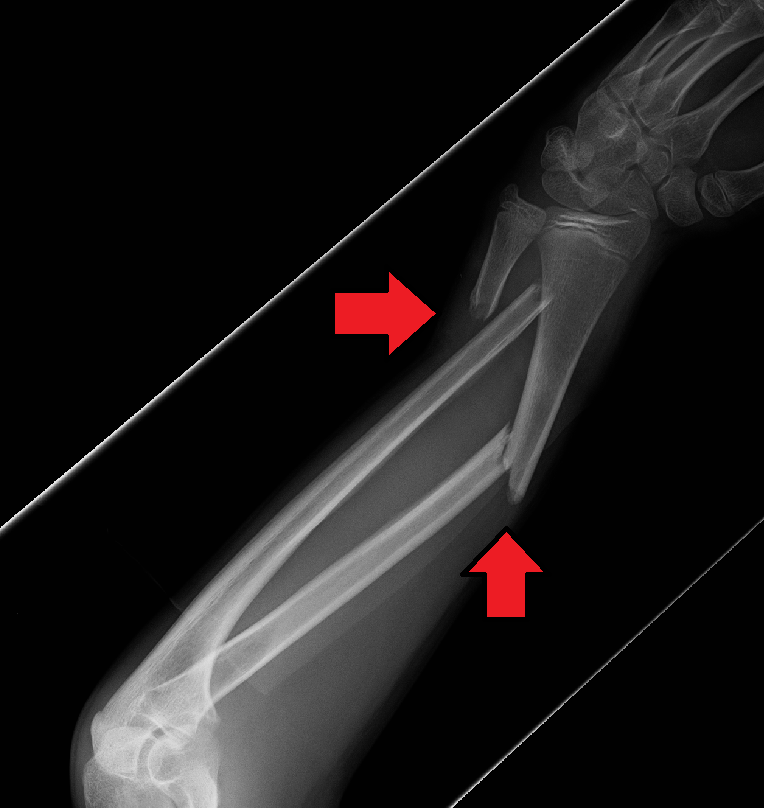

팔의 골절은 척골만 포함하는지(척골 골절), 요골만 포함하는지(요골 골절), 아니면 요골과 척골 둘 다 포함하는지(요척골 골절)에 따라 분류할 수 있다.